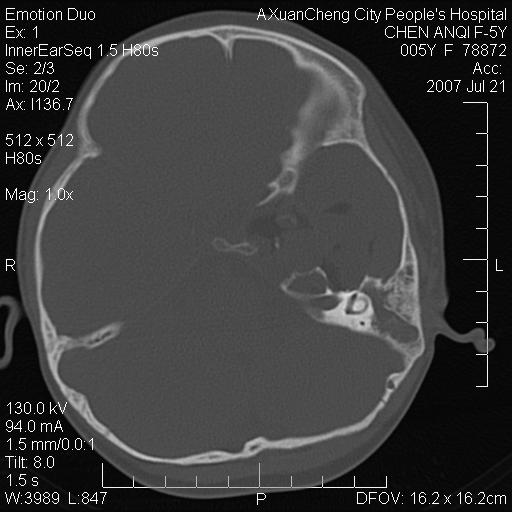

标题: PED0273:5岁,左耳流脓痛疼一周,颅底骨质破坏 [打印本页]

标题: PED0273:5岁,左耳流脓痛疼一周,颅底骨质破坏

患儿5岁,左耳流脓痛疼一周,左外耳道肉芽组织填塞 软组织窗显示病灶内结节状低密度影为气体密度

左侧中耳炎并胆脂瘤,左颞骨岩部骨质破坏并颅内感染积气。

考虑化脓性中耳乳突炎伴胆脂肪瘤形成并左颞叶感染,不除外合并嗜酸性肉芽肿.